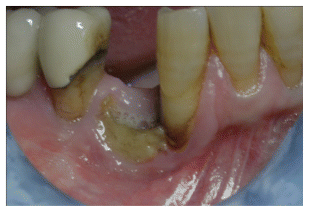

- Epithelial Healing:

Complete epithelialization was observed in 14 out of 15 patients within a median of 3 PRF applications (range: 2–8). In most cases, the first clinical signs of granulation tissue and epithelial closure appeared as early as the second visit. (Figure 2-3-4) - Pain Reduction: